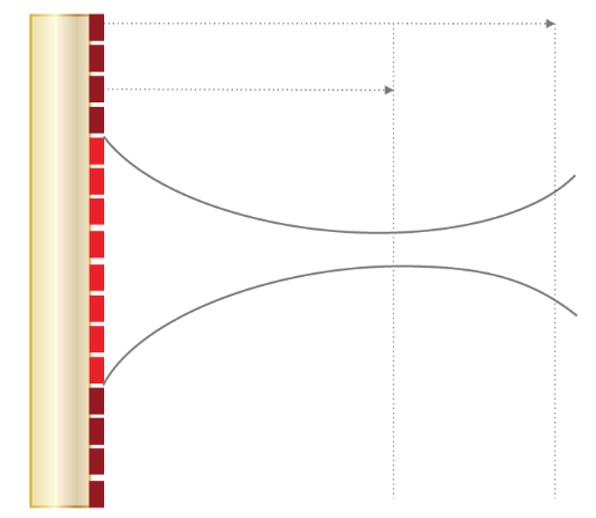

Lateral Resolution

As we mentioned previously, lateral resolution means the resolution of objects located side by side (perpendicular to the axis of the ultrasonic beam). The lateral resolution is directly related to the width of the ultrasound beam, which is inversely related to the ultrasonic frequency. It is the ability to distinguish between two separate objects that are close to each other and are in a direction perpendicular to the beam axis.

A high-frequency transducer emits a wave with short wavelength and reduced width of the ultrasound beam. The lateral resolution is weak when the 2 structures, side by side, are located in the same width of the beam. Since the return echoes overlap in this case, the two structures will appear as one in the corresponding image.

It is therefore important to choose high-frequency transducers, in order to keep the beam width as narrow as possible and achieve the best possible lateral resolution. However, attenuation also increases with frequency, so a compromise must be found between resolution and mitigation.

The beam width can be further reduced by adjusting the focal area. It is, therefore, useful to position the target structure in the focal zone to obtain the best possible lateral resolution. The beam diverges increasing its width while propagating in depth. It is possible to focus the ultrasound beam to obtain a narrow beam at the focal length, and thus improve the lateral resolution. Focusing can be accomplished either mechanically, or electronically via a multi-element array.